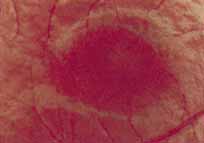

During the early stage of the dystrophy, when patients demonstrate a slight-to-moderate decrease in visual acuity and minimal color defects, there are minor or no visible fundus abnormalities. At most, the foveal reflex may be absent and there may be some increased granularity of the retinal pigment epithelium in the macula. Later, there is a decrease of visual acuity to the 20/400 range, oval atrophy of the macular retinal pigment epithelium (“beaten bronze” atrophy), and associated choroidal atrophy (Fig. 3). A characteristic bull's-eye maculopathy, similar to that seen in patients with chloroquine retinopathy, may also be seen.90 Photophobia, occasional nyctalopia, incomplete-to-complete color defects, and a central scotoma are often present. The symmetry of the process in both eyes is remarkable.